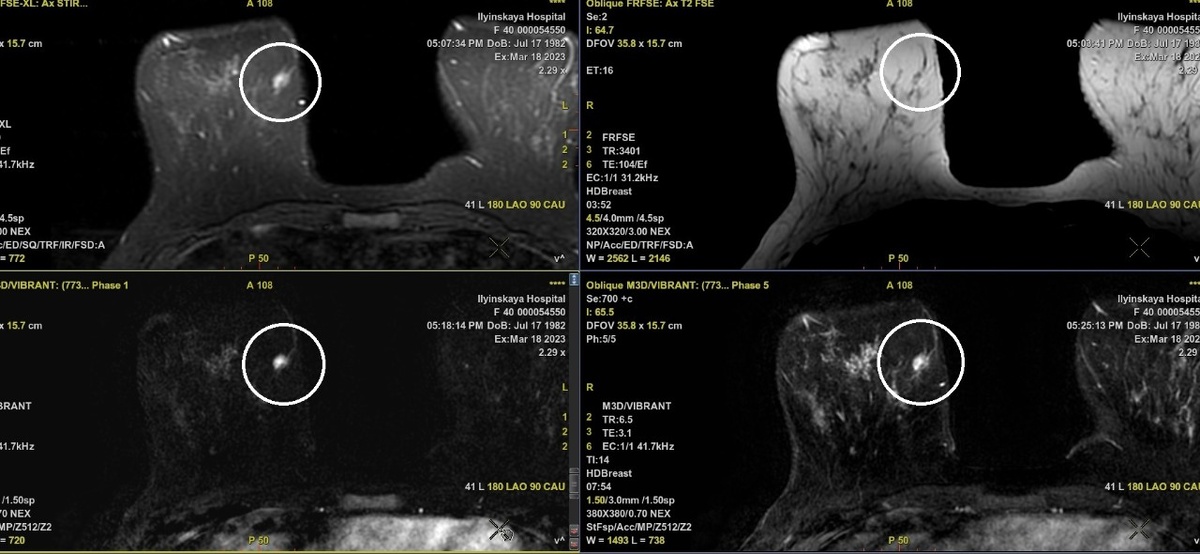

При УЗИ молочных желез также не были выявлены изменения, и с целью дообследования пациентке было назначено МРТ. При МРТ молочных желез с внутривенным контрастированием в левой железе не было выявлено никаких изменений (!), но в правой молочной железе в нижне-внутреннем квадранте отчетливо определялось патологическое образование 9.0 х 7.5 мм, быстро и неоднородно накапливающее контрастное в-во, с признаками его вымывания в отсроченную фазу контрастирования (рис.2). Все это свидетельствовало в пользу злокачественного новообразования.

Для верификации диагноза показана биопсия образования под контролем метода, который выявляет его более отчетливо. Но образование отчётливо визуализировалось только при МРТ.